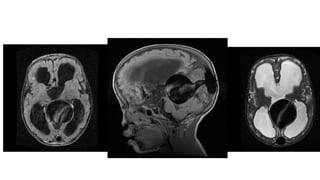

Pineoblastoma • They aresmall round blue cell tumours located in the pineal region. • They closely resemble (both on imaging and histology) like other blue cells like medulloblastoma and retinoblastoma. • They are the most aggressive (WHO grade 4) • They are typically found in young children, with only a slight female predilection

• 31.

• There isa well established association with hereditary retinoblastoma where • Trilateral retinoblastoma- Bilateral retinoblastoma and a pineoblastoma • Quadrilateral retinoblastoma- Bilateral retinoblastoma, pineoblastoma and a supracellar pineoblastoma

CT Findings • Relativelylarge tumours • Slight hyperdense (high cellular tumor) • Classically, shows or "exploded" similar to pineocytomas ( In contrast, pineal germinomas tend to engulf pineal calcification)

• 33.

MRI Findings • Irregularmasses often with evidence of invasion into the adjacent brain • T1: Isointense to hypointense to adjacent brain • T2 • Isointense to adjacent brain • areas of cyst formation or necrosis may be present • T1 C+ (Gd): vivid heterogeneous enhancement

• 34.

• DWI/ADC- restricteddiffusion due to dense cellular packing • Central cystic necrosis is sometimes present and thus can roughly mimic a pineal cyst, although the latter should have a smooth, thin wall • Screening of the whole neural axis is necessary as CSF seeding is seen in 45% of cases.

• #30 highest grade tumour among pineal parenchymal tumours and are considered WHO grade 4 tumours (M:F 0.7:1; similar to other pineal parenchymal tumours), which is in contrast to the male predominance seen in pineal germinomas)

• #31 Trilateral retinoblastoma refers to the combination of retinoblastoma (usually bilateral) and pineoblastoma. This association highlights the close relationship between these highly aggressive small round blue cell tumors. Approximately 5-15% .

• #35 A large mass ( * ) centered on the pineal region elvates, splays and partially engulfs the internal cerebral veins (blue arrows). Pineal calcifications (red arrows) are best seen on CT and are located at the periphery of the mass.  Enhancing soft tissue is also seen filling the floor of the third ventricle (green arrows) and in the lateral ventricles (best seen in the left forntal horn - yellow arrow).

• #36  the pineal region shows a lobulated soft tissue mass lesion, it measures about 2.9 X 2.7 X 2.7 cm in its main diameters  the lesion shows mildly hypointense T1 and hyperintense T2 / FLAIR signal, with inhomogenous post-contrast enhancement the lesion shows mild restricted diffusion a suspected small signal void focus is seen at its peripheral anterior aspect of the lesion (which was evident on CT study that was available with the patient)  the lesion is seen compressing the superior portion of the cerebral aqueduct with moderate supratentorial hydrocephalus as well as transependymal CSF permeation mild downward herniation of the cerebellar tonsils is noted